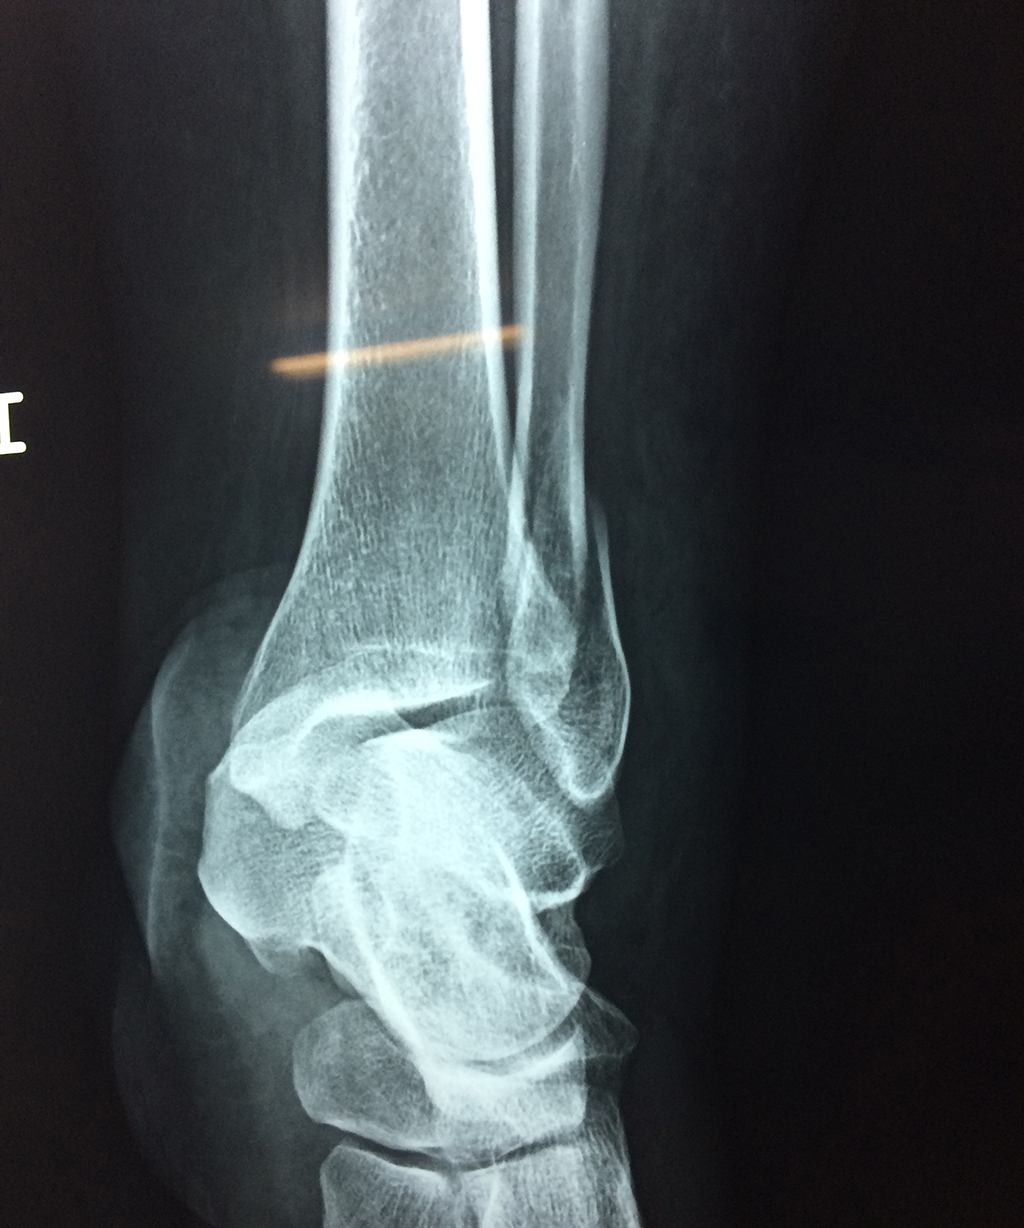

Algunas fracturas de tobillo pueden requerir cirugía si:

- Los extremos de los huesos están desalineados entre sí (desplazados).

- La fractura se extiende hasta la articulación del tobillo (fractura intra-articular).

- Los tendones o ligamentos (tejidos que sujetan los músculos y los huesos entre sí) están rotos.